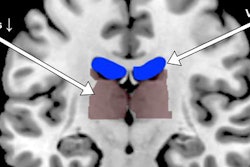

To improve this process, Cao and colleagues used their machine-learning algorithm to examine brain fMRI scans of individuals with or without schizophrenia. By assessing the functional connections between the superior temporal cortex and other regions of the brain, the algorithm was able to identify schizophrenia with 78.6% accuracy. It also predicted whether a patient would respond to the antipsychotic drug risperidone with 82.5% accuracy (Mol Psychiatry, June 19, 2018).